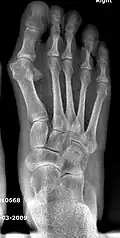

Fig. 8a. Painful hallux valgus and metatarsus primus varus deformity recurrence of left foot after osteotomy surgery

1. For recurrence correction after osteotomy procedure (Fig. 8)

Late deformity recurrence can happen after osteotomy (bone-breaking) procedures because osteotomy surgeries do not specifically stabilize first metatarsal bone.